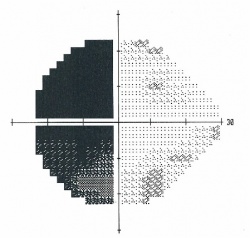

![]()

Figure 1. Humphrey visual field 24-2 showing a bitemporal hemianopsia.

Figure 2. Goldmann visual field showing a bitemporal hemianopsia.[38]

Chiasmal Field Deficits

Characteristically lesions at the level of the optic chiasm produce a bitemporal hemianopia. Pituitary adenomas, which grow upward from the pituitary stalk, compress the chiasm from below, which preferentially involves the inferior, nasal, and macular nerve fibers. This corresponds to superior, bitemporal, and central vision loss. While these field defects typically respect the vertical midline, pituitary adenomas large enough to cause compression tend to also reduce visual acuity and cause diffuse central depression on automated and Goldmann perimetry.[5] Vison loss due to compression first affects the superotemporal visual fields, then inferotemporal, inferonasal and finally superonasal fields.[31]